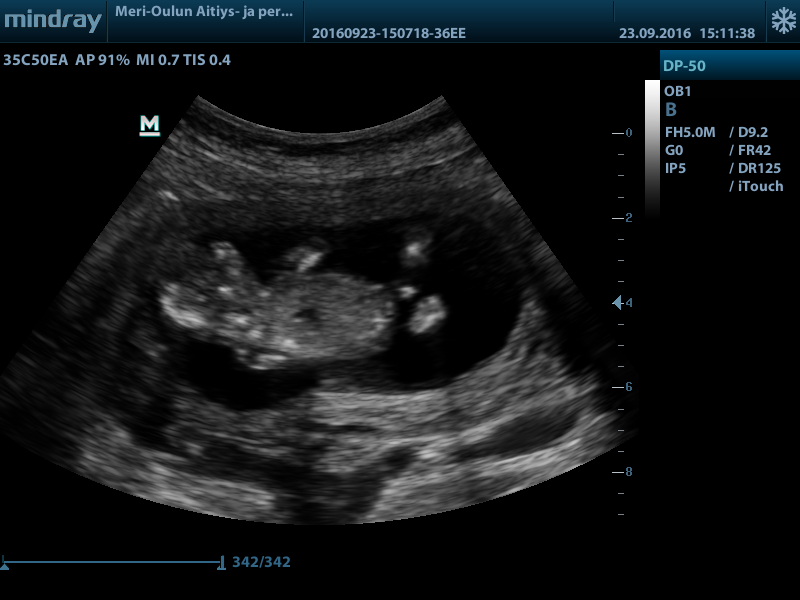

Hi! Would love your thoughts regarding the gender. Boy or girl? (And maybe why, I'm really new at this.. )

Top of the baby isn't the best for nub guessing but at 13 weeks girl parts wouldn't be so...large... At that gestation. I'm a few of the pictures I am almost positive I see testicles too so my guess is boy :) will actually be a little shocked if you hear girl please update when you know!